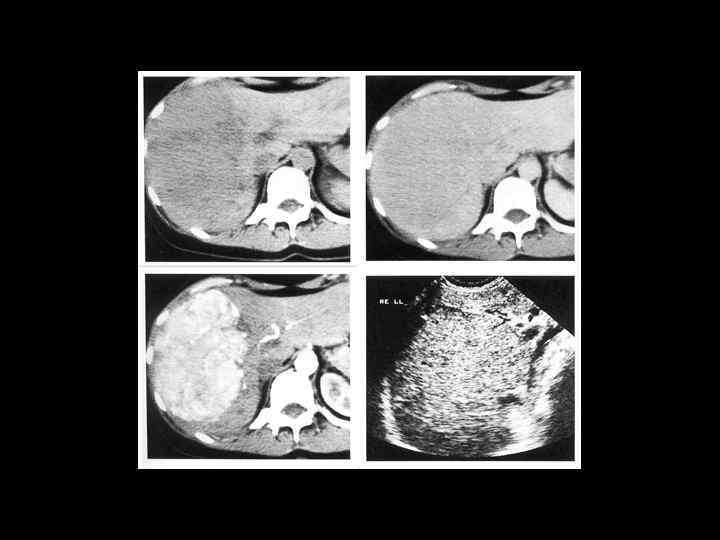

АКТУАЛЬНЫЕ ВОПРОСЫ РЕНТГЕНОЛОГИИ ЛУЧЕВАЯ ДИАГНОСТИКА ОЧАГОВЫХ ПОРАЖЕНИЙ ПЕЧЕНИ КАВЕРНОЗНАЯ ГЕМАНГИОМА Компьютерно-томографическая семиотика: - ограниченный участок пониженой плотности (до 50 -30 ед Н) - границы могут быть ровными, но нечеткими - после введения РКВ - характерный феномен усиления плотности от периферии к центру в течении нескольких минут после внутривенного введения РКВ

Клиническое наблюдение. Пациентка С. , 1953 г. р.

Та же пациентка